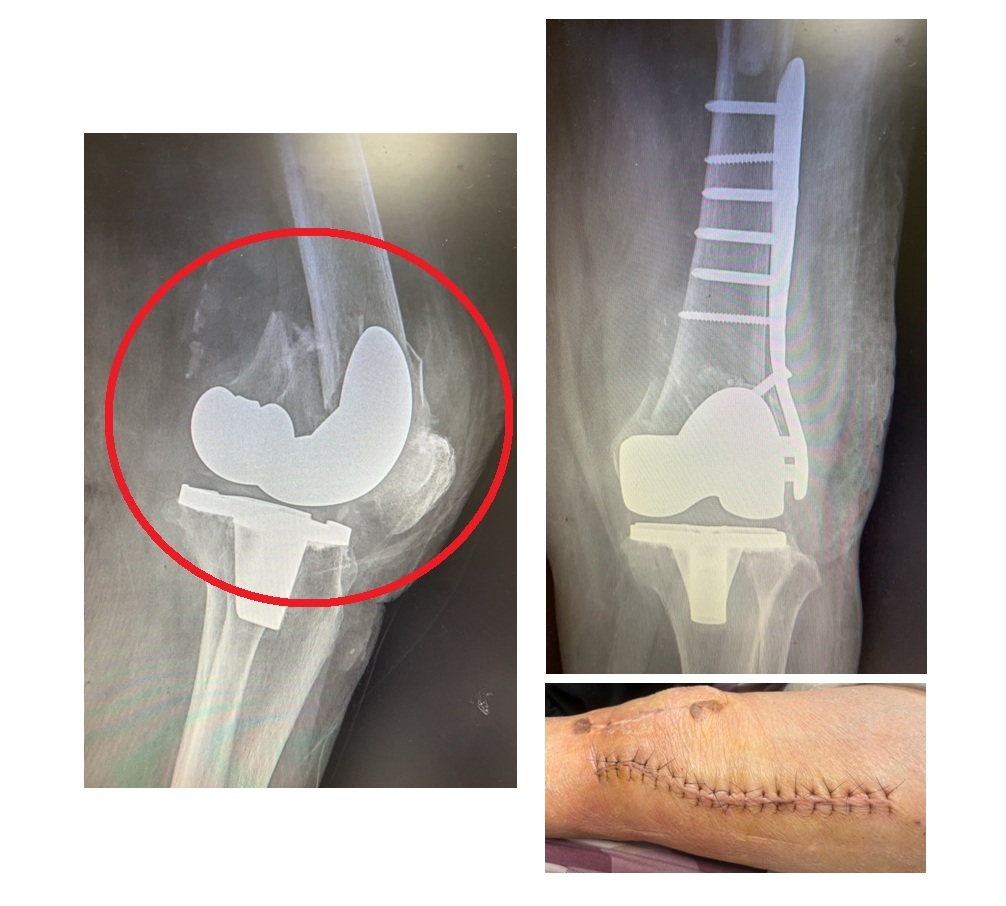

大千綜合醫院骨科醫師容志雄分享近日治療的兩個案例,第一位是93歲的奶奶,20年前曾接受人工膝關節置換手術,使用傳統的人工墊片,近日因跌倒導致整個膝關節骨頭破裂,必須以傳統開刀方式進行治療,用鋼板鋼釘來支撐骨頭,加上病人骨質疏鬆嚴重,另需以石膏副木固定三個月,雖然後續骨頭痊癒也可行動,但她的膝關節彎曲功能卻因此變差。另一位病人是71歲的女士,不小心踩到地上的青苔滑倒,因為6年前她接受人工膝關節置換手術時,使用的是高貼合度的人工膝關節墊片,因此跌倒後雖然關節脫臼錯位,但骨頭整體沒有大問題,只需在輕微的麻醉下將錯位的關節拉回,並針對膝關節股骨內踝撕裂性骨折進行副木固定,一個月就恢復正常,膝關節功能也不會受影響。

93歲的奶奶使用傳統人工墊片,跌倒後骨頭破裂(左圖紅圈處),須以傳統開刀方式治療(右方上下圖)。